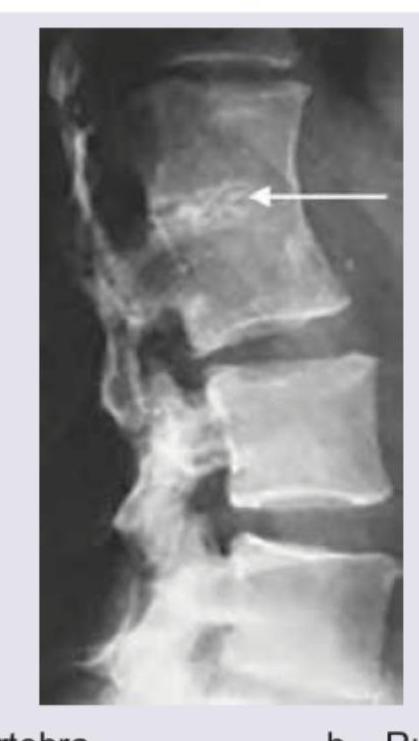

What is the correct diagnosis for the image shown?

Explanation: ***Fish vertebra*** - The image indicates **biconcave vertebral bodies** with a central depression, mimicking the appearance of a **fish vertebra**. This shape results from bone softening conditions, leading to compression of the vertebral body by the turgid intervertebral discs. - This finding is classically associated with **osteoporosis** or **osteomalacia**, where the bone mineral density is reduced making the vertebrae more susceptible to this type of deformation. *Hemivertebra* - A hemivertebra is a **congenital anomaly** where only half of a vertebral body forms, causing a wedge-shaped vertebra and often leading to **scoliosis**. - The image does not show a malformed, wedge-shaped vertebral body; instead, it shows a **biconcave deformity** of a fully formed vertebra. *Rugger jersey spine* - Rugger jersey spine refers to the appearance of alternating lucent and sclerotic bands on the superior and inferior endplates of vertebral bodies, resembling the stripes on a rugby jersey. - This finding is characteristic of **renal osteodystrophy** due to secondary hyperparathyroidism, which is not depicted in the given image. *Block vertebra* - A block vertebra is a **congenital or acquired fusion** of two or more adjacent vertebral bodies, resulting in a single, enlarged vertebral segment with rudimentary or absent intervertebral discs. - The image clearly shows distinct vertebral bodies with intervening discs, albeit distorted, and no evidence of fusion.